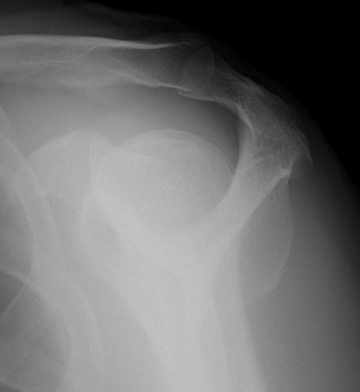

X-ray

| AP | Supraspinatus outlet view | Axillary lateral |

|---|---|---|

|

Sclerosis greater tuberosity / acromion Lateral Acromion spur |

Acromial morphology | Os acromiale |

![]() |